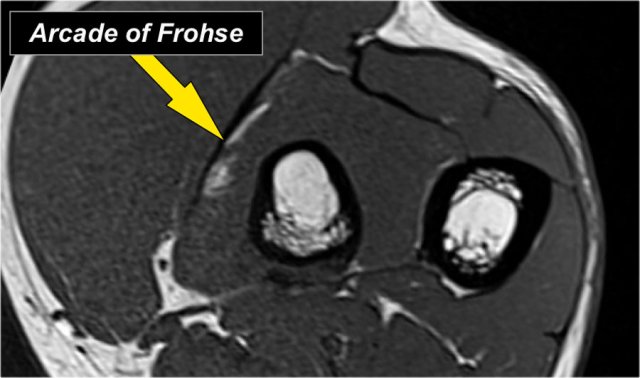

The radial nerve can be best identified at the level of the radial head, where you can see superficial and deep branches in the radial tunnel (arrows).

This is a very consistent place to find the radial nerve.

The deep radial branches form the posterior interosseus nerve which penetrates the supinator muscle at the arcade of Frohse (arrow).

The findings are:

1. On the upper left T1W-image there is high signal fat within the extensor muscles with loss of muscle bulk which indicates fatty atrophy.

2. The axial image on the upper right shows a mass more proximally in the supinator muscle.

3. The sagittal images confirm that this is a lipoma.

So the atrophy is a result of compression of the posterior interosseous nerve, which is a branch of the radial nerve.